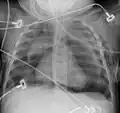

Pneumomediastinum is uncommon and occurs when air leaks into the mediastinum. The diagnosis can be confirmed via chest X-ray showing a radiolucent outline around the heart and mediastinum or via CT scanning of the thorax.

Pneumomediastinum and right sided pneumothorax post first rib fracture in a mountain biking accident. -

Pneumomediastinum with angel wing sign[15] - Pneumomediastinum as seen on ultrasound[16]